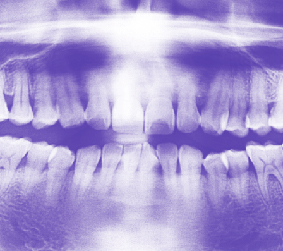

À½½ÄÀÇ ¸ÀÀ» ¾Ë°í Àß°Ô ºÎ½¤ÁÖ´Â Ä¡¾Æ

ưưÇÑ Ä¡¾Æ´Â ¿µ¾çºÐ °ñ°í·ç ¼·ÃëÇÒ ¼ö ÀÖ°Ô ÇØÁà Áö³­ ¿©¸§Ã¶Àº À¯³­È÷ »ç¿ì³ª ÅÁ °°Àº ¹«´õÀ§¿Í Æø¿°, ±×¸®°í ÀÚÁÖ ºñ°¡ ³»·È´Ù. ±×·¯³ª ÀÌÁ¦ °¡À»ÀÇ ½ÃÀÛÀÎ 9¿ù¿¡ Á¢¾îµé¾ú´Ù. .... ¤ÓÀ̹̳ª ±âÀÚ 2010-09-10